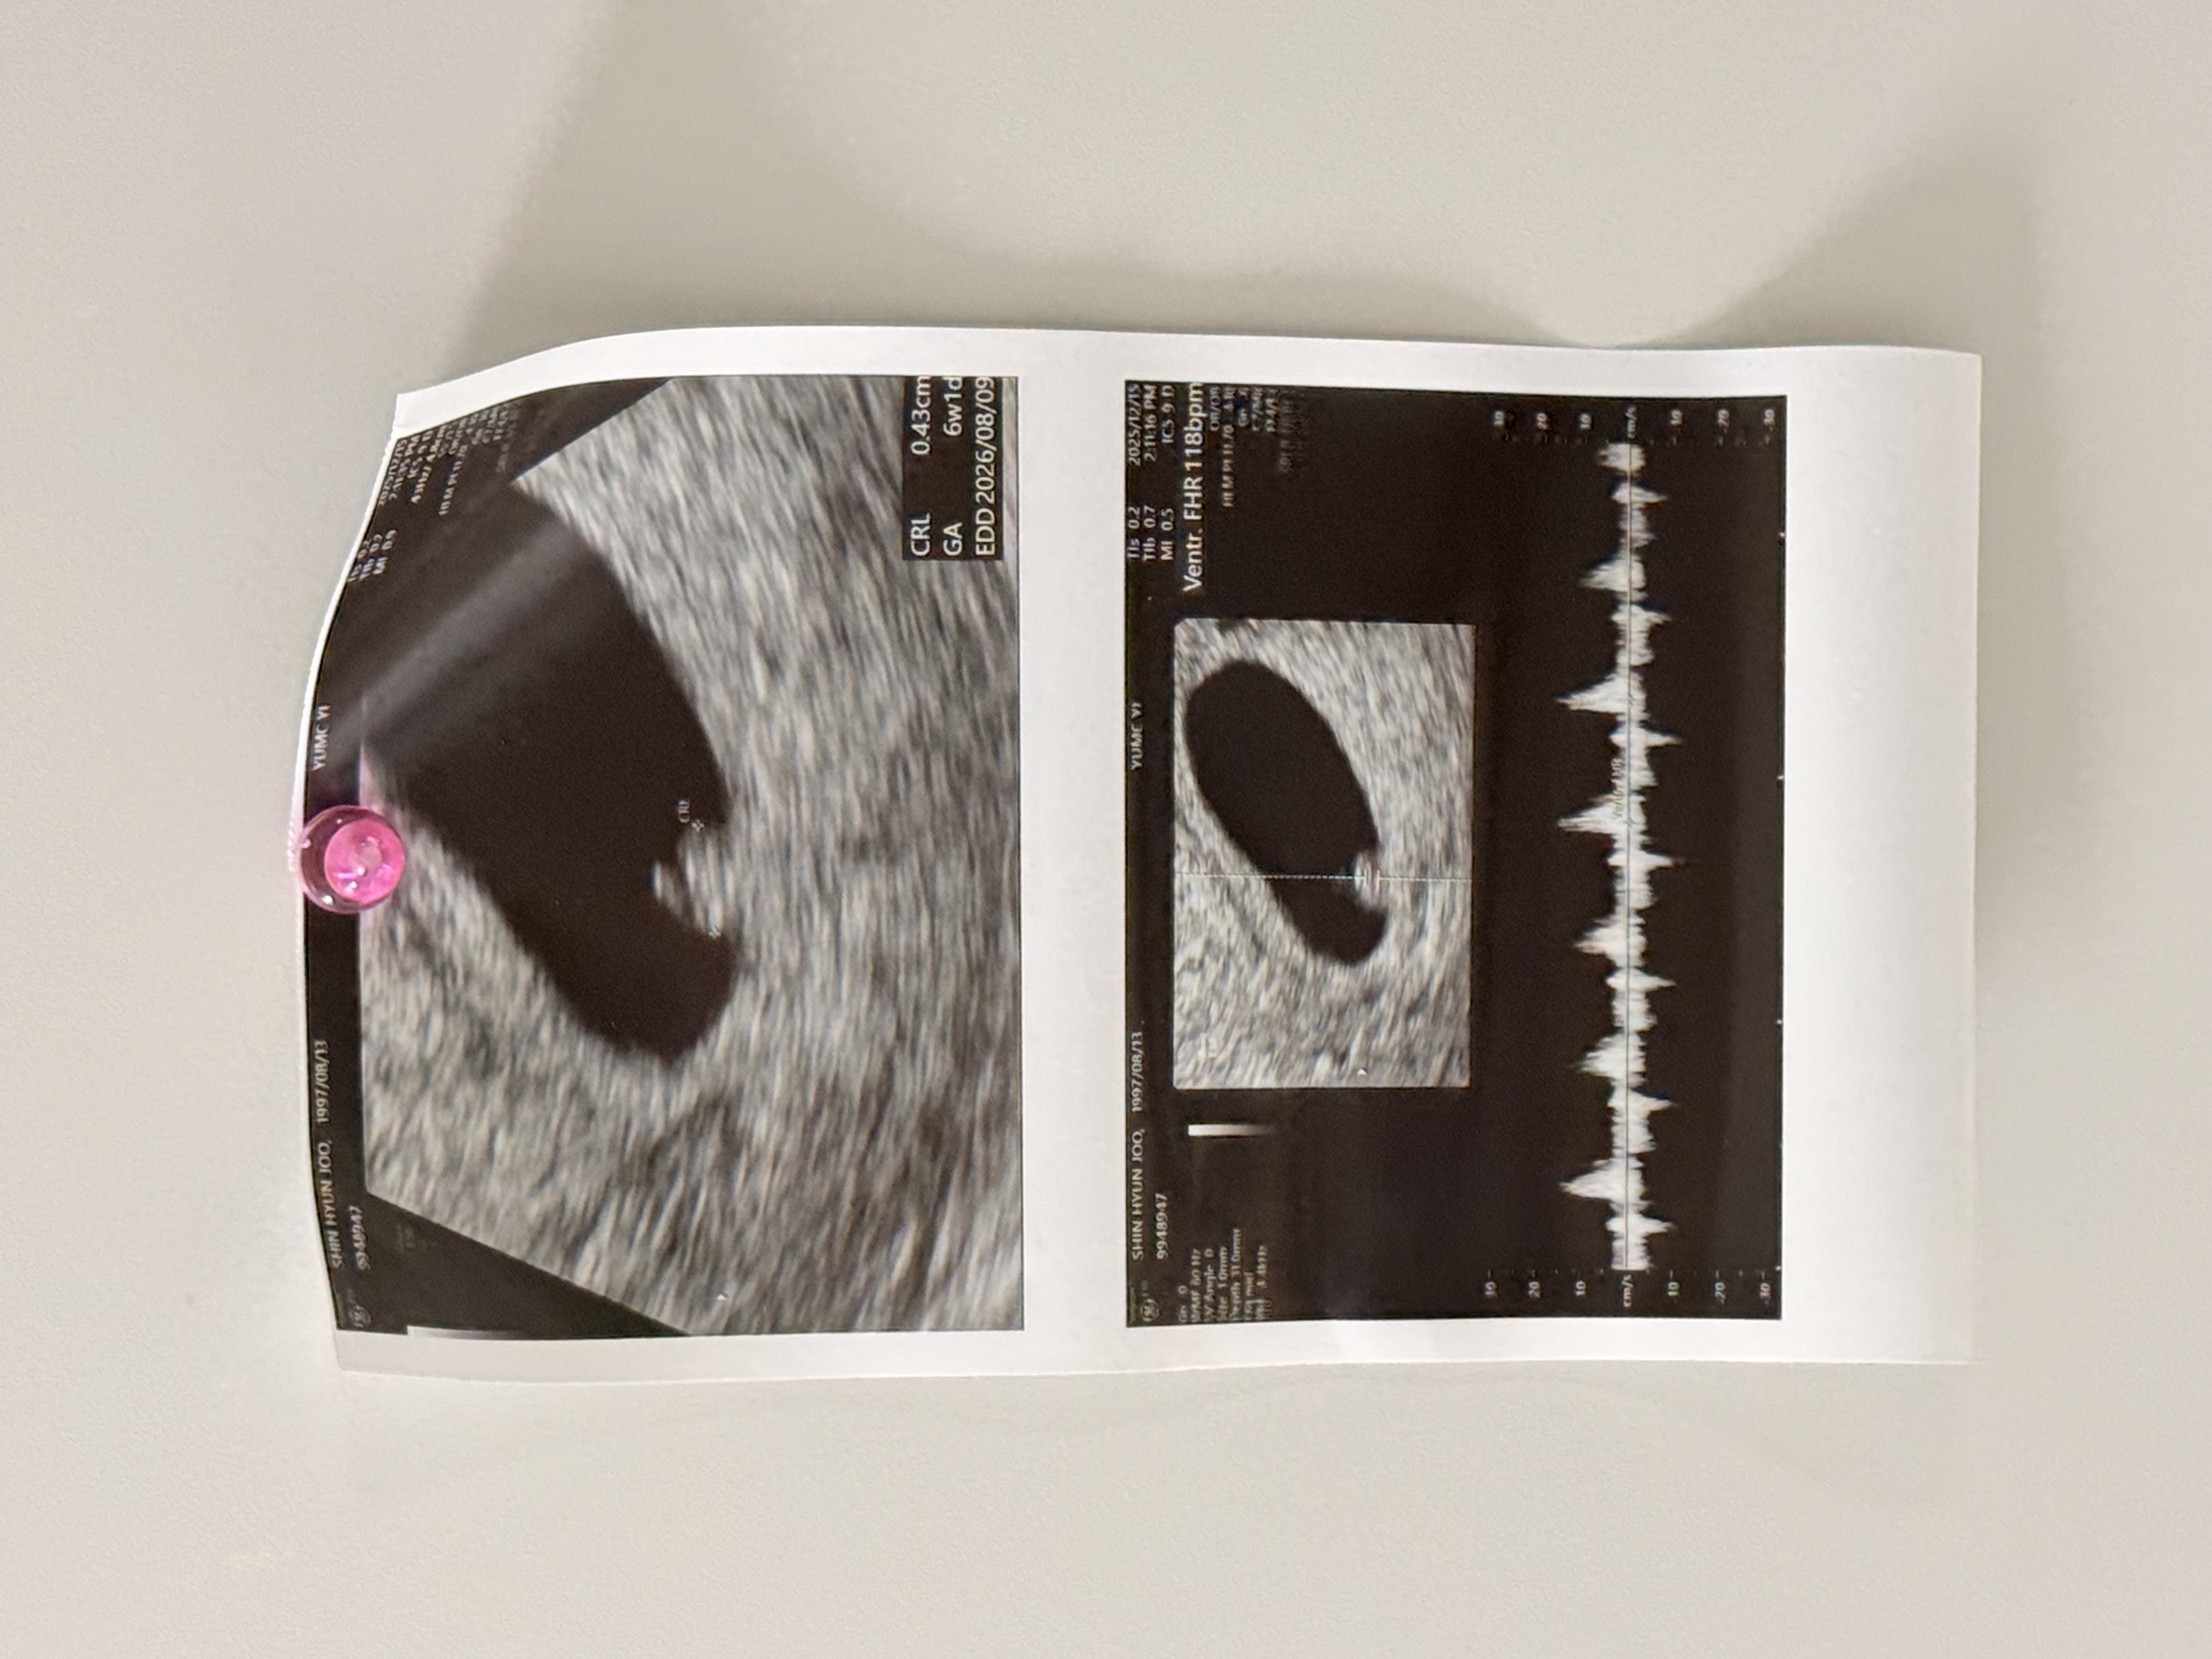

어제 딱 6주 되는 날이었거든요! 원래 부인과 검진 예약인데 임신소식을 안지 얼마 안돼서 간김에 아가 볼 수 있게 됐어요 ㅎㅎ 아마 분만도 복용약(정신과)때문에 여기서 하지 않을까 싶어요 초음파 보자마자 심장 반짝거리는거에 울컥 하고, 막상 심장소리 들을 땐 너무 신기해서 눈물 쏙 들어가는거 있죠! 사이즈도 6주 1일이어서 주수랑 비슷해서 안도되고, 작은 심장이 118bpm으로 뛰는 것도 너무 신기해요..🥹🥹🥹 비록 대학병원이라 직접 영상 찍느라 손이 부들부들 다리가 부들부들해서 잘 못찍었지만 ㅎㅎ 그래도 건강하게 자라고 있는 모습 보니 마음이 한결 놓여요 🥹 서브병원에서는 다음주 수요일쯤 오라고 했는데, 8주 가까이 금요일에 가는게 나을지 좀 더 일찍 화요일에 가는게 나을지 너무 행복한 고민중이에요 ☺️ 아직 주변에 임밍아웃을 많이 안해서 베동에 정말 글 많이 남기게 되는 것 같아요! 베동 동기분들도 건강하게 이 시기 지내보아요 🤍